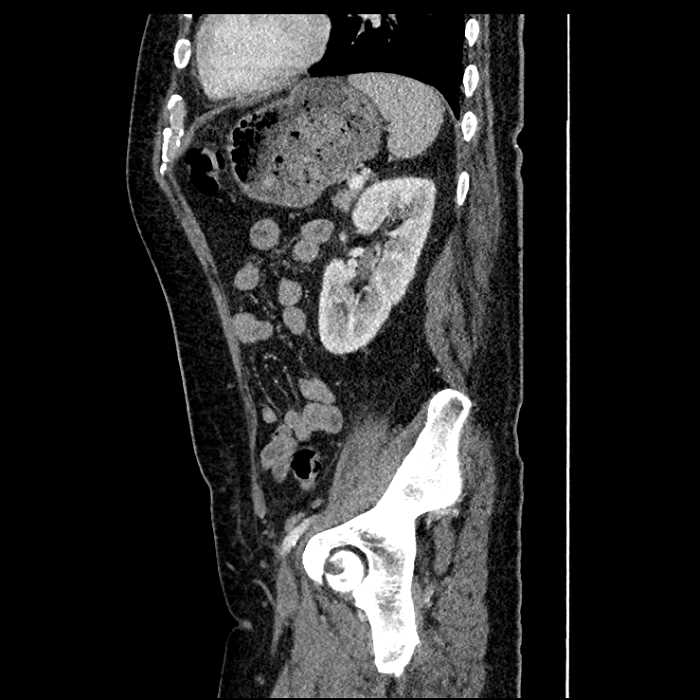

Age: 63

Sex: Male

Indication: Abdominal pain

• Large fluid density structure in hepatic segments 7 and 8 measuring 10 x 7 x 7 cm with internal septation and circumferential ill-defined low density compatible with edema

• Peripherally enhancing subcapsular collections along the anterior margin of the left hepatic lobe measuring 3 x 1 cm and 2 x 1 cm

• Clearly marginated fluid density structure in segment 7 and several other scattered tiny hypodensities, which likely represent cysts

Acute sigmoid diverticulitis complicated by a small contained perforation and a large abscess in the right hepatic lobe. Additional small subcapsular abscesses along the anterior margin of the left hepatic lobe.

Additionally, loss of the normal fat plane between the peridiverticular collection and adjacent thickened loops of small bowel raises the potential for an enterocolonic fistula.

• The classic CT imaging appearance is a double target sign with internal low density surrounded by an internal enhancing rim (capsule) and a low density external rim (edema)

Hepatic abscess showing the double target sign with low density internally surrounded by a thin inner enhancing rim (red arrow) and ill-defined outer low density rim (yellow arrow). Blue arrow indicates an internal septation. Red arrows: additional smaller subcapsular abscesses. Red arrow: focal contained perforation associated with diverticulitis.